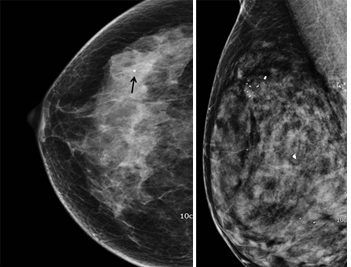

À¯¹æ ÃÔ¿µ¿¡¼ º¸ÀÌ´Â ´ëºÎºÐÀÇ ¼®È¸È´Â ¾Ï°ú °ü·Ã ¾ø´Â ¾ç¼ºÀÔ´Ï´Ù.

Áõ·Ê - ¾ç¼º ¼®È¸È

ÇÏÁö¸¸ ¾ÏÀÌ ÀǽɵǴ ¼®È¸ÈÀÇ °æ¿ìµµ Àֱ⠶§¹®¿¡ ¹Ýµå½Ã Àü¹®°¡¿Í »ó´ãÀÌ ÇÊ¿äÇÕ´Ï´Ù.

Áõ·Ê - À¯¹æ ÃÔ¿µ¿¡¼ °üÂûµÇ´Â ¹Ì¼¼¼®È¸È ±ºÁý